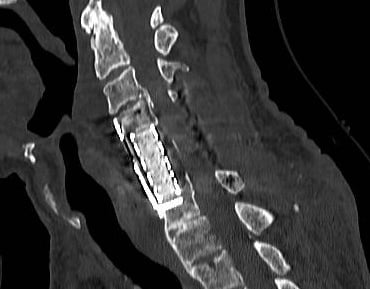

Neurocirurgia Coluna

Intervenções seguras para problemas na coluna vertebral.